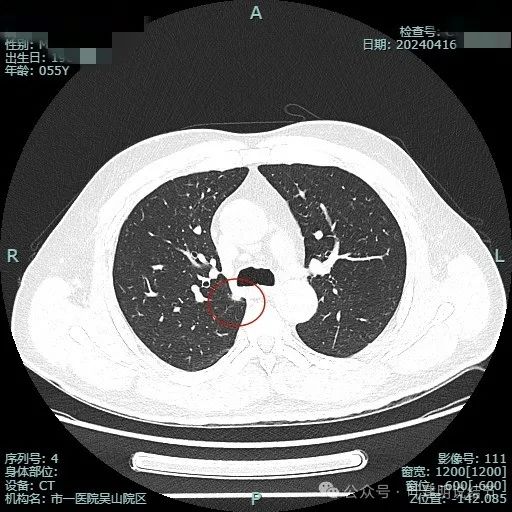

结节毛刺明显,而且是细毛刺。

有微血管走向病灶,结节与纵隔侧紧贴,但胸膜牵拉不明显。